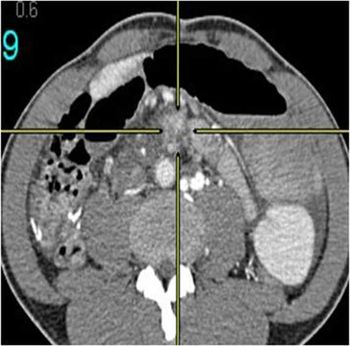

Clinical History: An 84-year-old male patient, known case of HTN and dyslipidemia, complaining of dysphasia for three months. Anorexia and vomiting. Diagnosed as esophageal adenocarcinoma outside for evaluation.